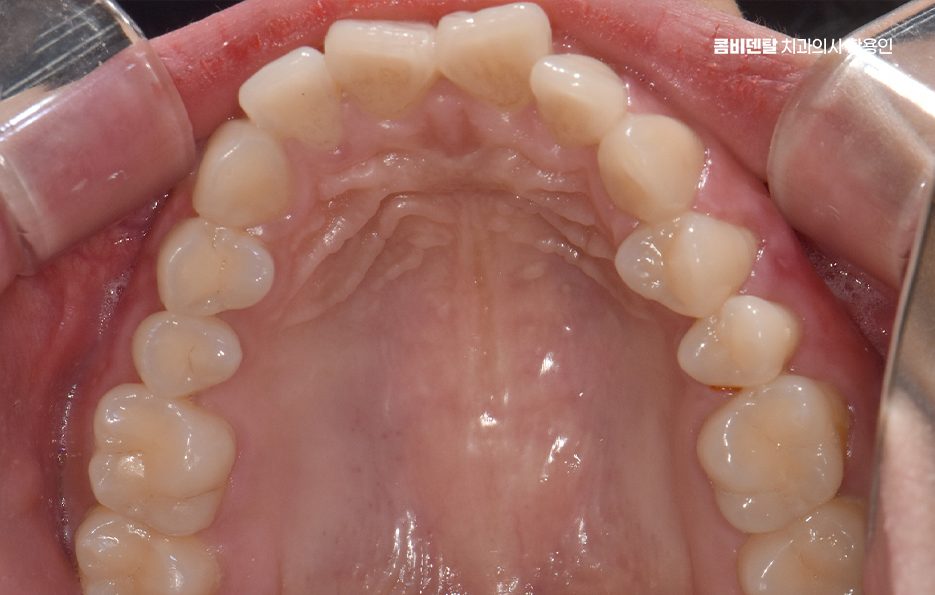

돌출입 팔자주름 교정 치아를 어떻게 움직이느냐에 따라 얼굴 인상이 달라지는 것인데 돌출입 교정은 일반적으로 소구치 네 개를 발치한 후, 앞니를 뒤쪽으로 밀어넣고 악궁을 재배열하는 방식으로 진행되며 앞니가 뒤로 이동하고 자연스럽게 입술이 들어가게 되고, 입술 돌출도가 줄어들면서 얼굴이 전반적으로 부드럽고 조화로운 느낌으로 바뀔 수 있어요

그렇다고 무조건 발치를 해야 하는 건 아니며 케이스에 따라 발치 없이도 돌출입이 개선되는 경우도 있는데 예를 들어, 돌출의 정도가 경미하거나 전체적인 치열에 여유 공간이 있다면 비발치 교정으로도 앞니를 어느 정도 뒤로 이동시킬 수 있어요. 다만 대부분의 돌출입 교정에서는 발치가 동반돼야 제대로 된 입술 라인과 얼굴 변화가 가능하며 교정에서 발치는 단순히 치아를 빼는 행위가 아니라, 치아를 움직일 수 있는 공간을 확보하는 중요한 수단이기 때문이라 할 수 있었어요